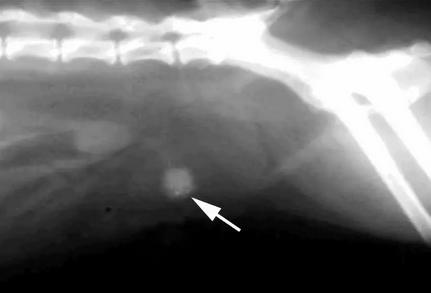

X射线:腹部X射线,寻找膀胱结石。如下图:

(注:X射线无法准确确定是由鸟粪石晶体形成的结石,还是有草酸钙晶体形成的结石,需进行尿液分析。)